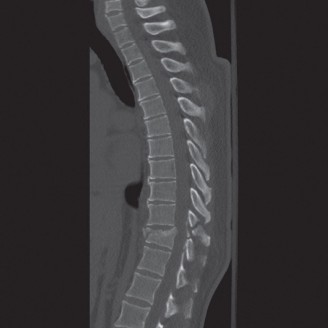

Upon his return five years later, the imaging profile was drastically different. Standing lateral radiographs now revealed a Meyerding Grade 2 spondylolisthesis at L5-S1, indicating that the L5 vertebral body had translated anteriorly by 25% to 50% over the sacral promontory. Furthermore, there was a noticeable collapse of the L5-S1 intervertebral disc space, signifying advanced degenerative changes secondary to the altered biomechanics and chronic instability. We also meticulously measured the patient's spinopelvic parameters on a standing 36-inch scoliosis cassette. His Pelvic Incidence (PI) was measured at 65 degrees (high), which mathematically dictates a higher Sacral Slope (SS) and Pelvic Tilt (PT). A high PI is a known biomechanical risk factor for the progression of spondylolisthesis, as it creates a steeper lumbosacral shear angle, placing immense anterior translational force across the compromised L5-S1 segment.

To evaluate the neural elements and the soft tissue structures, a comprehensive MRI of the lumbar spine without contrast was obtained. The T2-weighted sagittal and axial sequences confirmed the Grade 2 anterolisthesis and demonstrated severe bilateral foraminal stenosis at L5-S1. The exiting L5 nerve roots were severely compressed between the hypertrophied, fibrocartilaginous pseudarthrosis tissue of the pars defect dorsally, and the bulging, degenerated L5-S1 disc and superior endplate of S1 ventrally. Furthermore, the MRI revealed Modic Type II changes (fatty replacement of the subchondral bone marrow) in the adjacent vertebral endplates, confirming chronic biomechanical stress and discogenic degeneration. The central canal remained relatively patent, which is characteristic of isthmic spondylolisthesis, as the posterior neural arch is left behind during the anterior translation of the vertebral body.